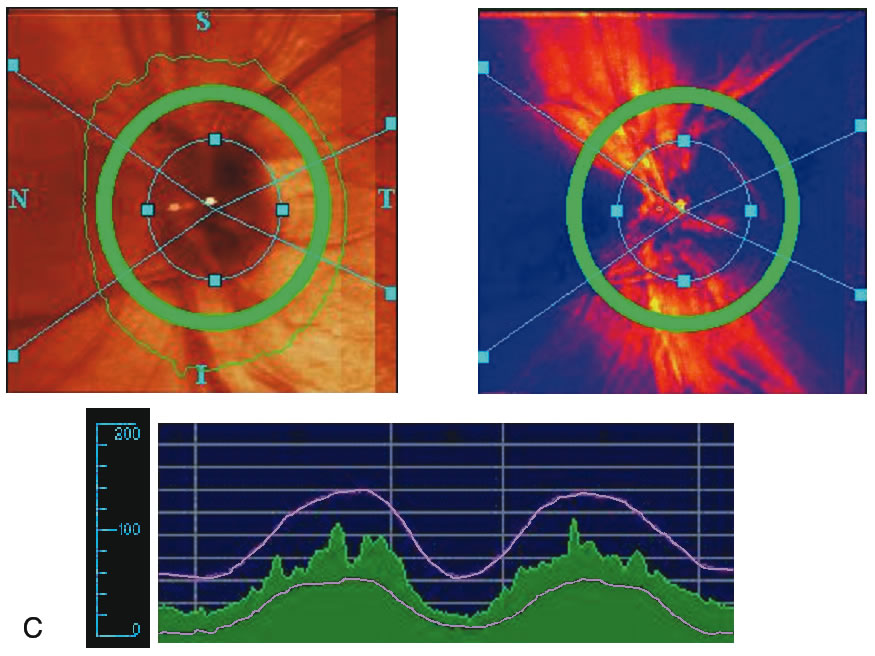

Stereometric parameters of optic nerve head topography are generated relative to the reference plane and include rim area, rim volume, cup area, cup volume, cup-to-disc ratio, mean RNFL thickness, and RNFL cross-sectional area. Parameters independent of the reference plane include mean and maximum cup depth, height variation contour, and cup shape measure (the statistical third moment of the distribution of all cup depth measurements). A characteristic sign in normal discs is the configuration of the contour line height display that demonstrates a double hump pattern corresponding to the thicker distribution of nerve fibers along the superior and inferior poles of the ONH (Fig. 4). Glaucomatous structural damage is characterized by a reduction of parameters that describe rim structures (area, volume) and indicate tissue loss (cup shape measure, cup volume, cup-to-disc ratio, cup steepness). As shown in Figure 5, glaucomatous alterations are typically associated with an asymmetrical or diffuse flattening of the contour line, or localized depressions corresponding to disc notches.